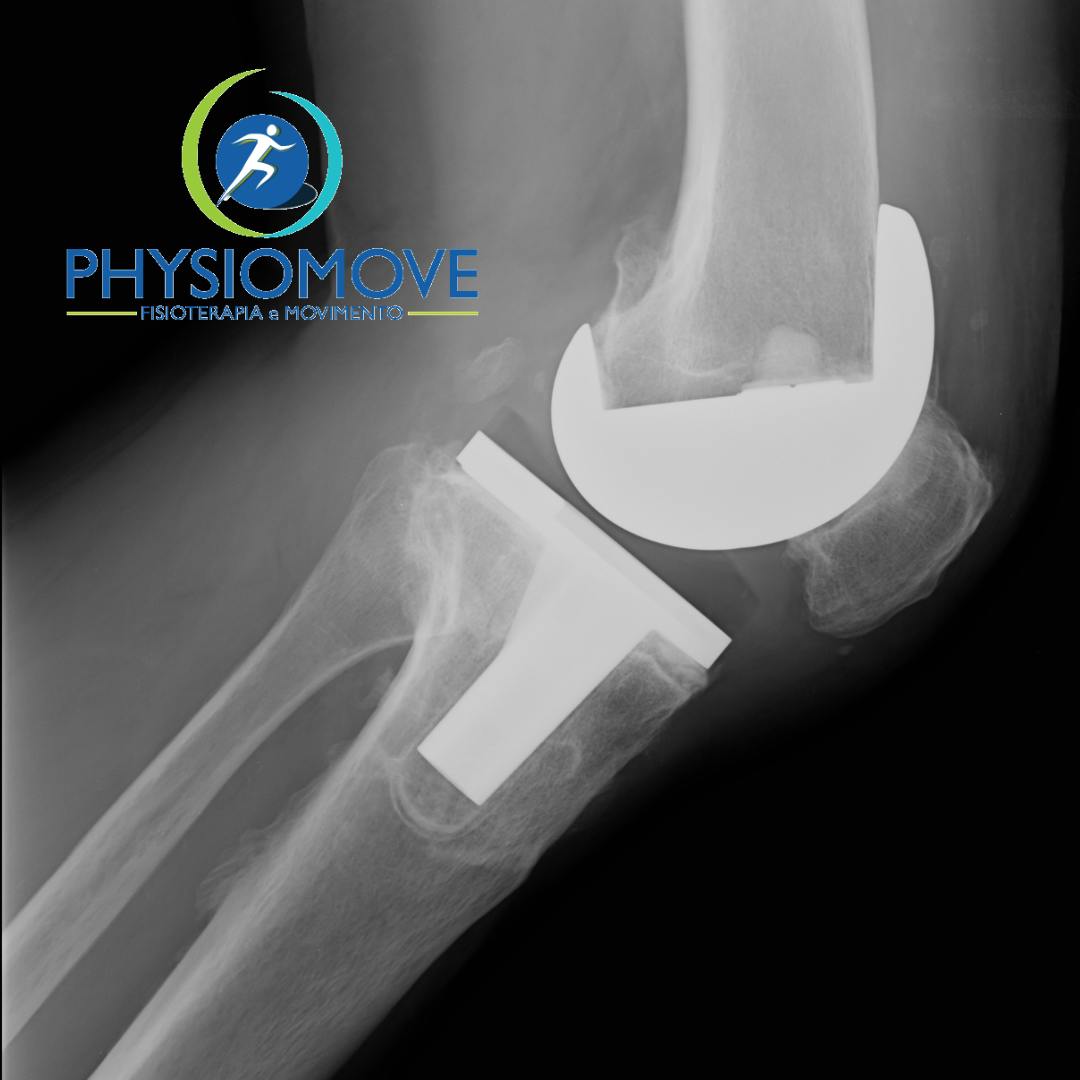

L'intervento chirurgico per inserimento di protesi di ginocchio rappresenta il primo passo verso un completo recupero. Dopo un intervento di...